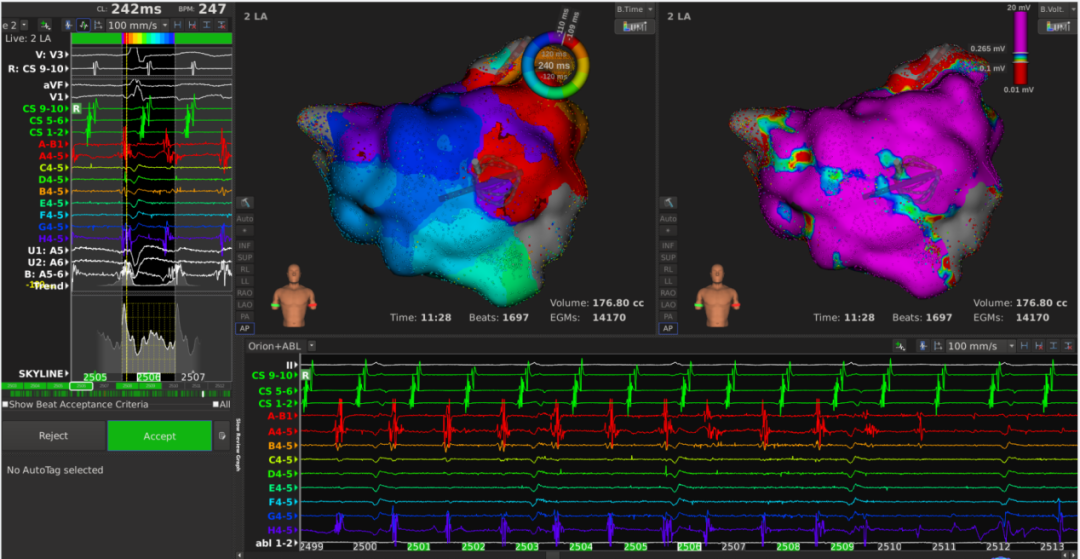

患者上台常规消毒铺巾,心电图显示心房扑动,周长为240ms,穿刺后,先行右房标测,标测结果显示最早激动点由冠状窦口传出,右房整体激动时间占心动过速周长约1/2。遂穿刺房间隔至左房,左房标测结果可见该心动过速绕二尖瓣进行折返,切换电压基质图可见顶部线已断,前壁线区域部分恢复,疤痕部分参与传导。遂先行消融前壁线,以40w 43℃功率模式放电,放电过程中平均单点阻抗下降约25Ω。至前壁线消融结束,心动过速周长延长至260ms. 再行消融二尖瓣峡部线,自瓣环拉至左下肺静脉过程中,DIRECTSENSE™局部阻抗监测技术显示单点阻抗下降约12Ω,心动过速周长逐渐延长至300ms,消融左下肺静脉口蓝点处,心动过速终止。巩固消融后,起博验证,二尖瓣峡线隔离成功。反复burst刺激诱发未见心动过速,本次手术结束。整台手术仅历时90分钟,病人术后感觉良好。

李岳春主任指出该病人病情复杂,能又快又好完成手术,Rhythmia三维标测系统和DIRECTSENSE™(局部阻抗监测技术)起到了关键作用,DIRECTSENSE™提供新的视角以评估导管贴靠,贴靠越好初始阻抗越高;本例手术中前壁线消融每个点阻抗下降10-15Ω,峡部线消融时平均每个点阻抗下降12Ω,DIRECTSENSE™在真实生物反馈的指导下提示有效消融终点,避免过度消融。

4、基质标测(顶部双电位,显示顶部线已断)

5、前壁碎裂电位